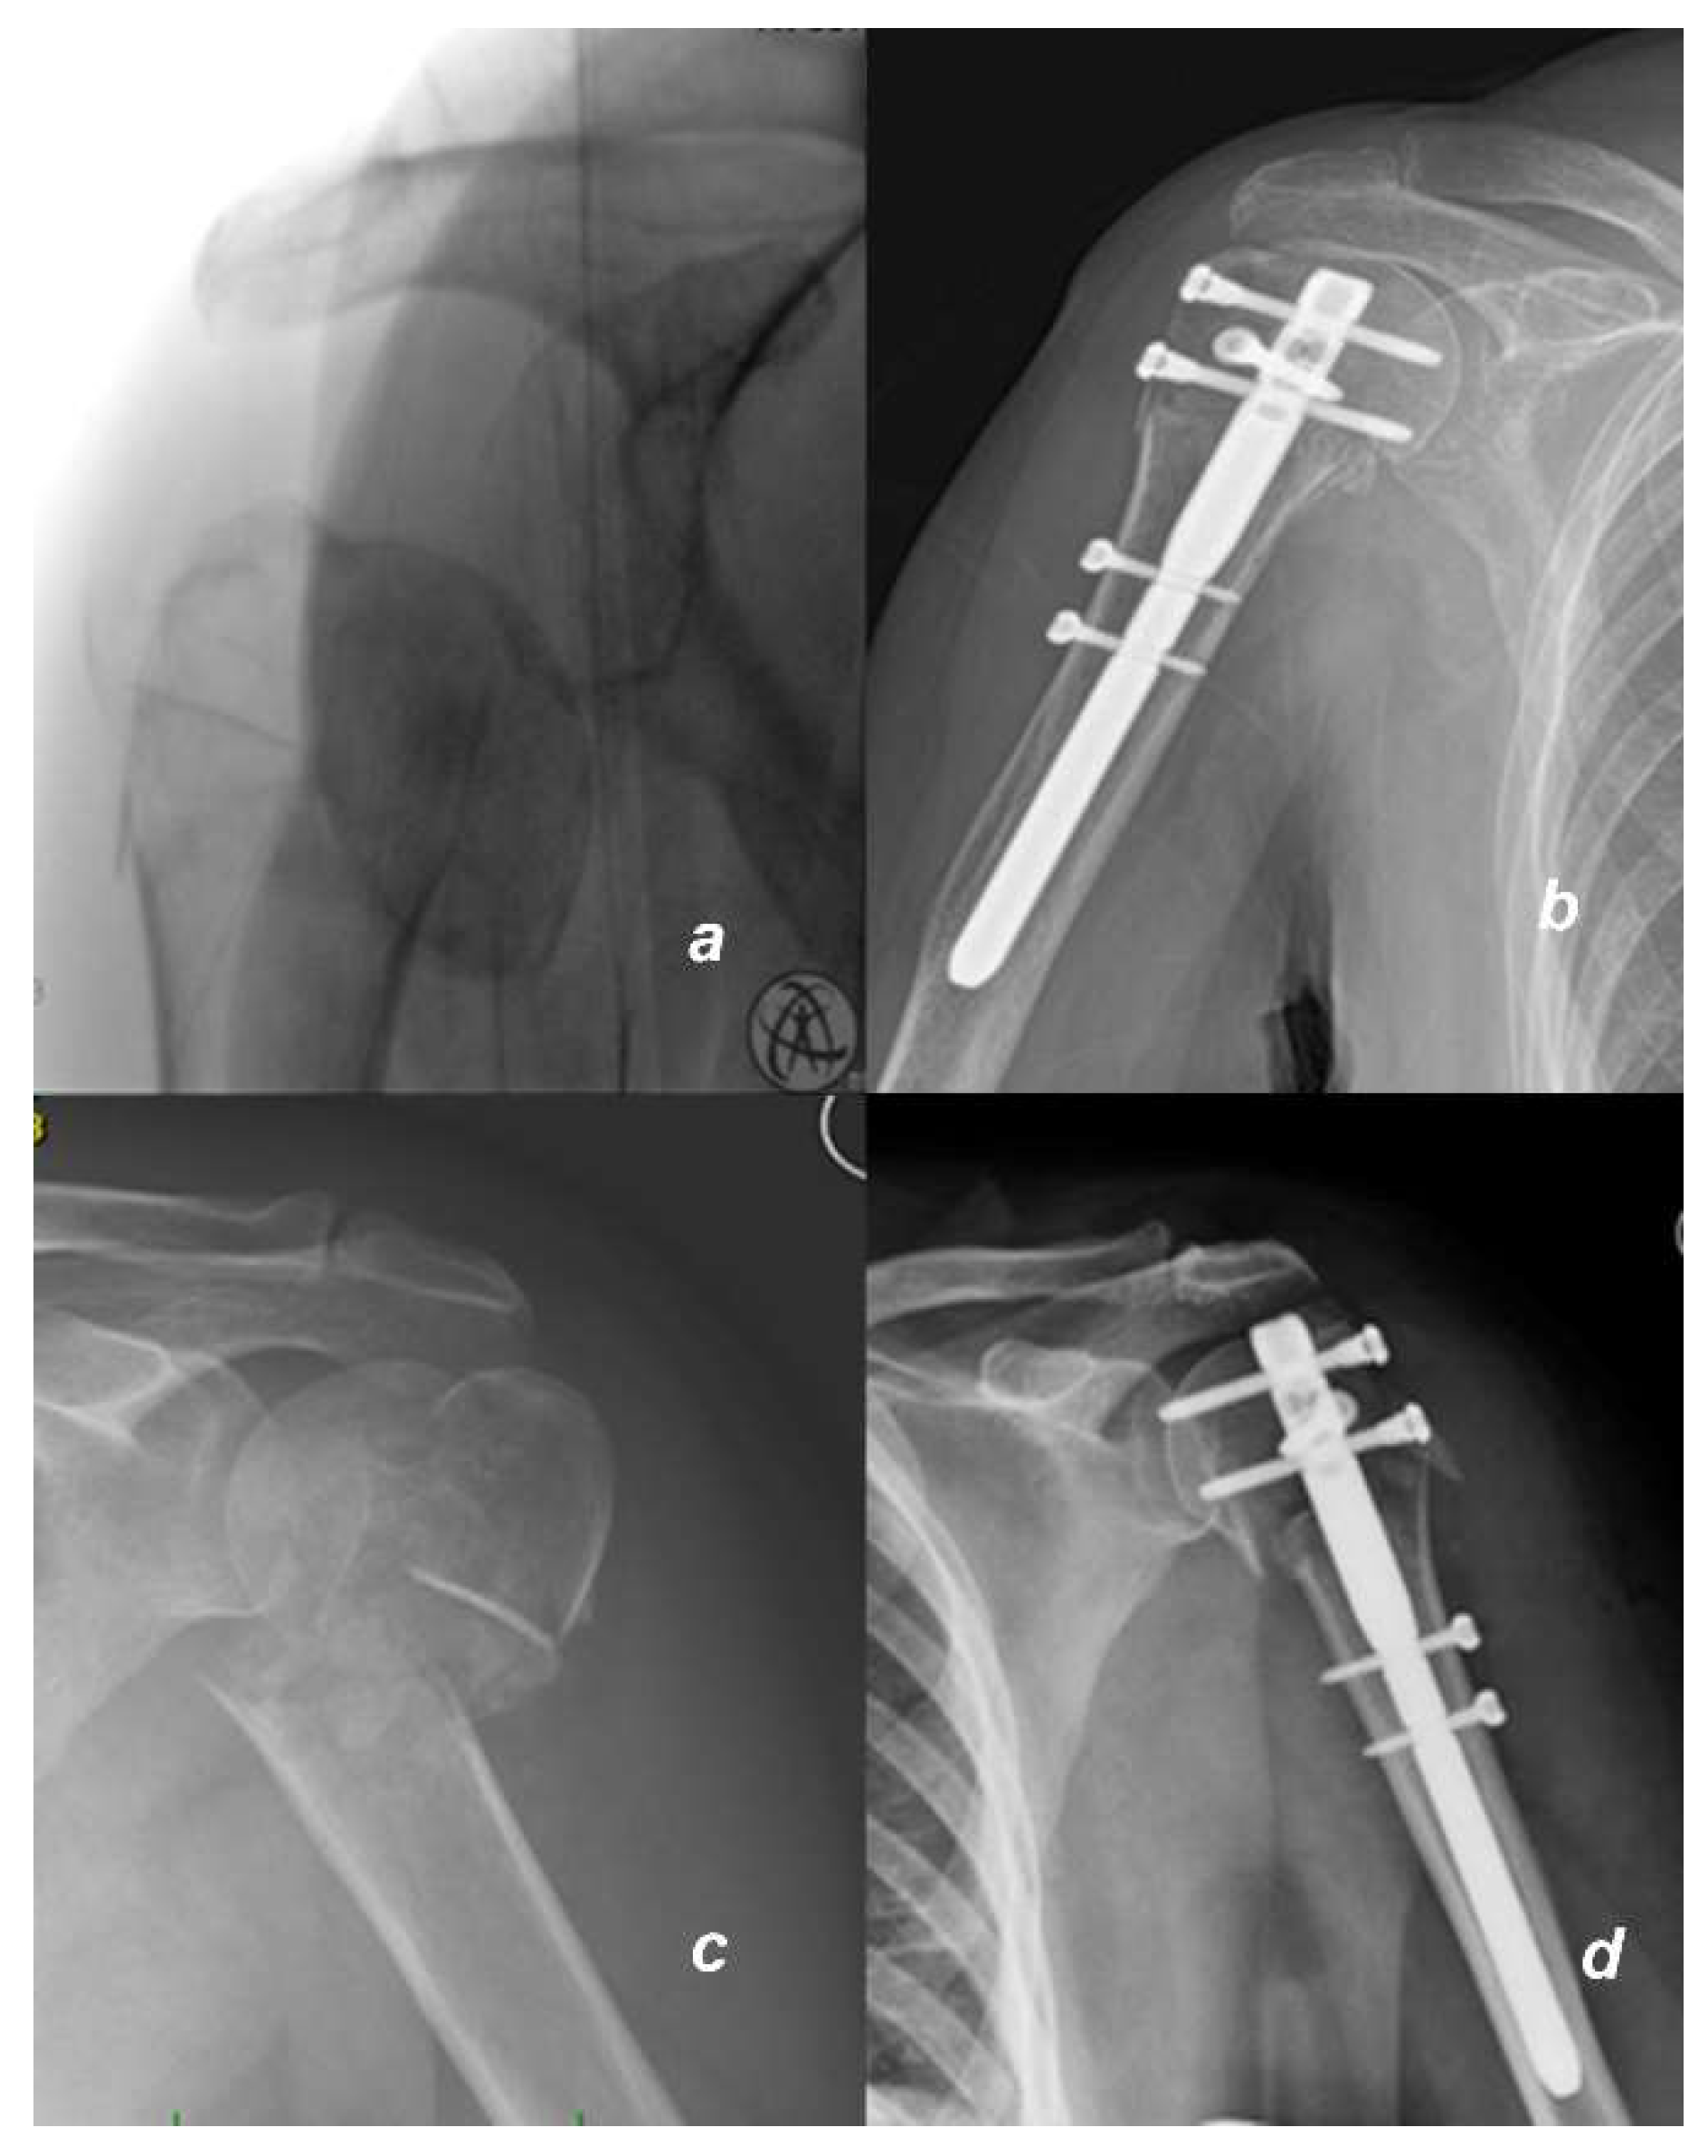

Figure 1.

X-rays of fractures and osteosyntheses in two patients: (a) Fracture of proximal humerus in a 57-years-old man with intraarticular fracture 11C1.1 (AO) before and (b) 12 weeks after osteosynthesis with humeral intramedullary nail; as the nail is not protruding, only proximal locking screws would be removed during arthrolysis; (c) a 65-year-old woman with a proximal humerus fracture 11C3.1 before and (d) 6 weeks after osteosynthesis; the nail is protruding. All screws including the nail would be removed during arthrolysis.